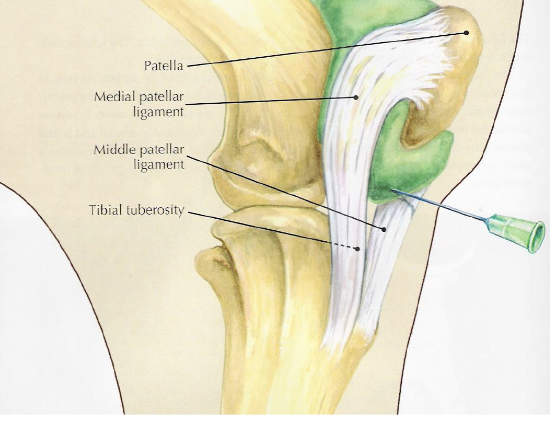

stifle

bones- patella, distal femur (+ medial and lateral trochlear ridges), tibia

lateral trochlear ridge of femur is shorter and smaller than medial

soft tissue structures- 3 patellar lig (medial middle lateral), medial & lateral collateral lig

joints- femoropatellar, medial femorotibial, lateral femorotibial

what is desensitized with a femoropatellar joint block

joint, in 65% of horses it can communicate w/ medial femorotibial joint but youre never sure which horses so you treat them all separately

what is desensitized with a medial femorotibial joint block

joint, +/- communication w/ femoropatellar joint in some horses

what is desensitized with a lateral femorotibial joint block

joint